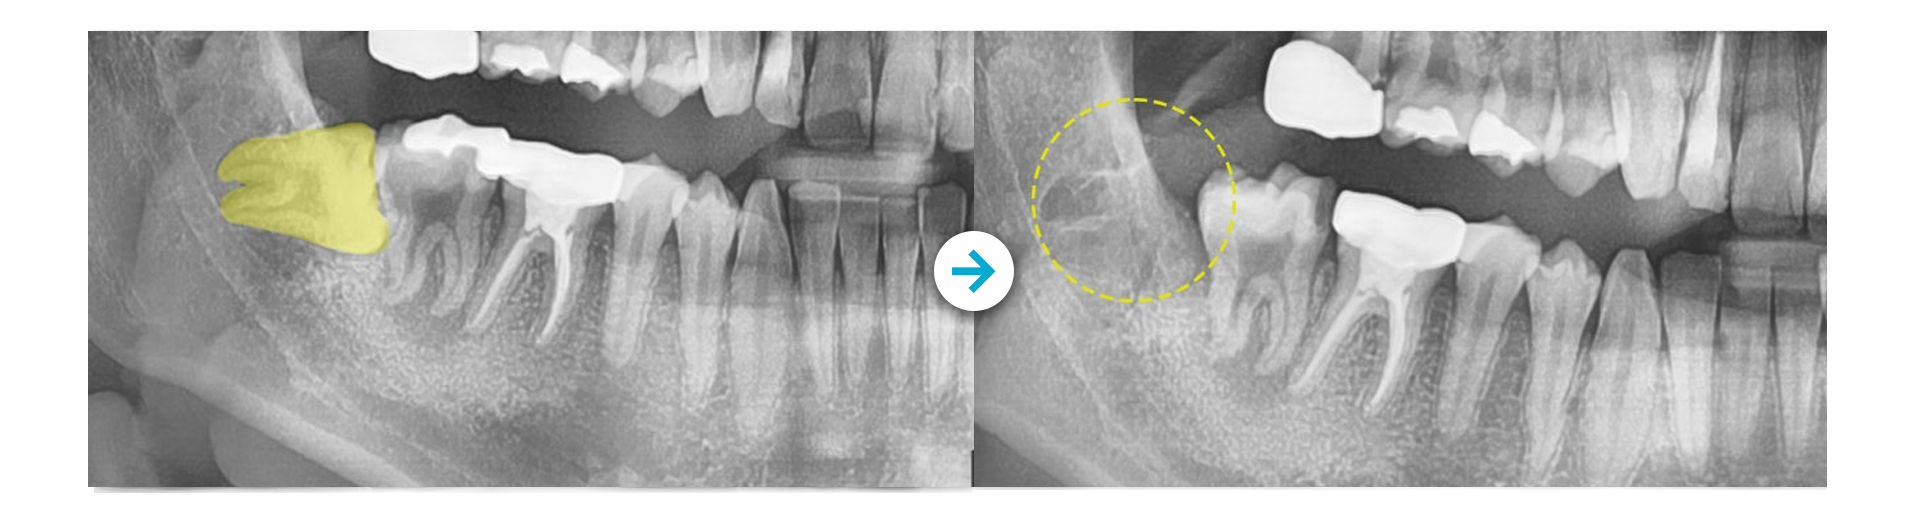

미소가득 매복사랑니 발치CASE ]

Before 사진 촬영일자: 2024.03.06 / After 사진 촬영일자: 2024.03.22

Before 사진 촬영일자: 2024.08.16 / After 사진 촬영일자: 2024.09.09

부작용 고지: 치아탈회, 치근흡수, 블랙트라이앵글, 치아재발 등

* 본원에서 치료 받으신 환자분의 사례로 2차적인 가공이 없으며, 환자분의 동의를 얻어 활용함을 안내드립니다.

개인에 따라 결과차이, 부작용 등이 발생할 수 있으므로 의료진과의 상담을 통해 신중히 결정하시기 바랍니다.